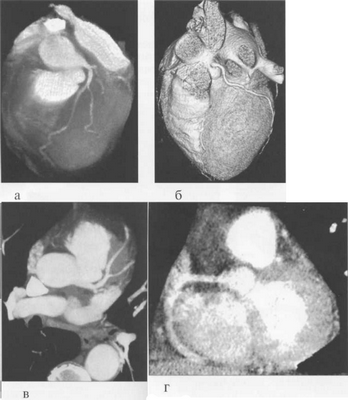

МСКТ в условиях внутривенного болюсного контрастирования позволяет визуализировать коронарные артерии (МСКТ-коронарография). Анализ состояния коронарных артерий выполняется сначала на аксиальных срезах (рис. 9.35). В постпроцессинговой обработке изображений используются различные виды реконструкций: многоплоскостные реформации (MPR), проекция максимальной интенсивности (MIP), трехмерные (VRT) (рис. 9.36).

Рис. 9.35. МСКТ-коронарограммы. Поперечные срезы.

Здесь и на рис. 9.36:

LM — ствол левой коронарной артерии, LAD — левая передняя нисходящая артерия, LCX — левая огибающая артерия, RCA — правая коронарная артерия.

Рис. 9.36. МСКТ-коронарограммы.

а, б — VRT-реконструкции; в — проекция максимальной интенсивности; г — многоплоскостная реформация.